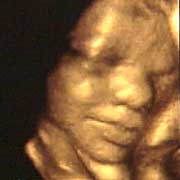

中新網(wǎng)9月13日電 英國天空新聞報(bào)道,英國科學(xué)家圖亞特·坎貝爾最近利用先進(jìn)的掃描技術(shù)清晰地拍下了孕婦子宮中胎兒的表情,透過他拍攝的照片,人們可以清楚的看到一個(gè)尚未降臨世間的小生命喜、怒、哀、樂的表情。

斯圖亞特.坎貝爾是倫敦著名的產(chǎn)科教授,他利用超聲掃描技術(shù)拍攝到了胎兒在子宮中打呵欠、眨眼、吮手指、哭泣甚至微笑的畫面,這些都為胎兒行為的研究提供了新的依據(jù),專家認(rèn)為,這一突破將推動(dòng)?jì)雰航】悼茖W(xué)的發(fā)展,包括對(duì)唐氏綜合癥等嬰幼兒疾病的診治將起到極大的推動(dòng)作用。

此前,醫(yī)學(xué)界一直認(rèn)為,嬰兒要到降生后才可以做出喜、怒、哀、樂的表情,要通過模仿母親才可以學(xué)會(huì)微笑。

坎貝爾教授說:“有個(gè)這種技術(shù),現(xiàn)在許多問題都可以進(jìn)行研究了。比如說,患有唐氏綜合癥的嬰兒和正常嬰兒的活動(dòng)方式是否一樣?胎兒是否因?yàn)楦吲d才笑?胎兒哭是否是因?yàn)樵谧訉m中受到打擾?既然我們都認(rèn)為子宮內(nèi)是一片黑暗,那胎兒為什么會(huì)眨眼呢?”(章田)